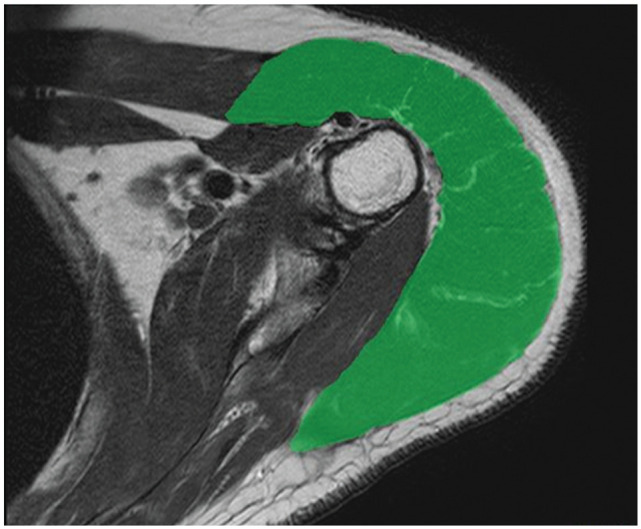

Methods: A total of 29 patients who underwent arthroscopic SCR using a fascia lata autograft were included. All received the same postoperative physical therapy. Active shoulder abduction and external rotation and American Shoulder and Elbow Surgeons (ASES) and Japanese Orthopaedic Association (JOA) scores were assessed preoperatively and 2 years postoperatively. Additionally, the acromiohumeral distance (AHD), rotator cuff tear size, and Goutallier/Fuchs and Hamada classifications were evaluated. Preoperative and postoperative deltoid muscle volumes were measured using a 3-dimensional reconstructed model from magnetic resonance imaging scans.